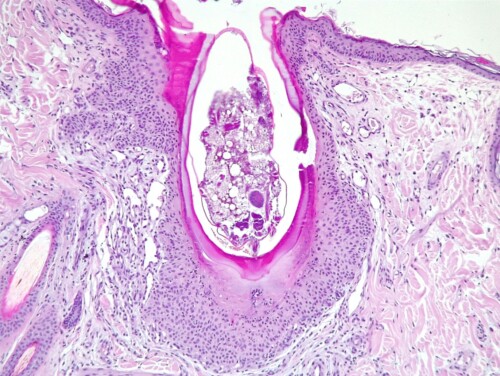

Photo 4 : vue à faible grossissement de cinq lésions. On peut déjà voir qu’il s’agit de lésions affectant la partie haute des follicules pileux, avec une paroi folliculaire hyperplasique et un contenu anormal.

Crédit photo : LAPVSO

L’aspect histologique est tout à fait particulier, dominé par des lésions folliculaires intéressant la partie haute des follicules pileux. La paroi folliculaire montre une hyperplasie pseudo-épithéliomateuse et une hyperkératose trichilemmale (kératine homogène rose vif). La paroi est entourée à ce niveau par un derme oedémateux (pâle) et néovascularisé (riche en capillaires). Dans chaque follicule lésionnel on observe un parasite de type acarien dont la tête et le rostre sont dirigés vers le fond du follicule pileux. Une section permet de distinguer une pièce buccale du parasite, allongée en forme de paille, l’histosiphon, qui plonge dans un secteur liquéfié et inflammatoire de la gaine folliculaire sous-jacente, la chambre de digestion. Chaque parasite est entouré par une coque épaisse, vitreuse et plus ou moins basophile et minéralisée, ouverte sur l’extérieur avec des extrémités recourbées en « lyre ». A distance de ces follicules lésionnels le tégument ne montre pas de lésions significatives.

Le différentiel histologique est inexistant car cette présentation est pathognomonique d’une dermatose parasitaire unique en son genre chez le chien : la straelensiose. Il s’agit d’une folliculite proliférative due à une infestation folliculaire par des larves enkystées de l’acarien Straelensia cynotis.